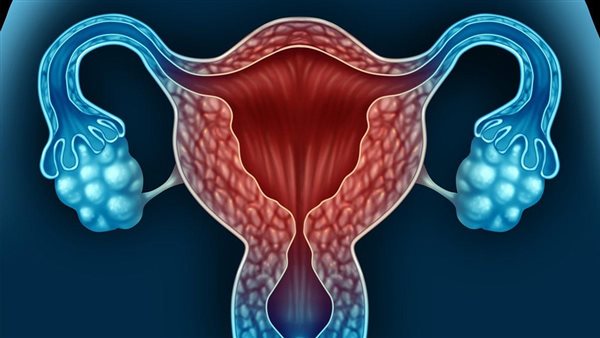

تقدم علمي كبير بشأن العلاج غير الهرموني لمرض بطانة الرحم

تعاني حوالي 200 مليون امرأة حول العالم من التهاب بطانة الرحم، وهي حالة تُسبب نمو أنسجة من بطانة الرحم في أماكن خارجها، وقد تكون هذه الحالة مؤلمة للغاية وتساهم في العقم.